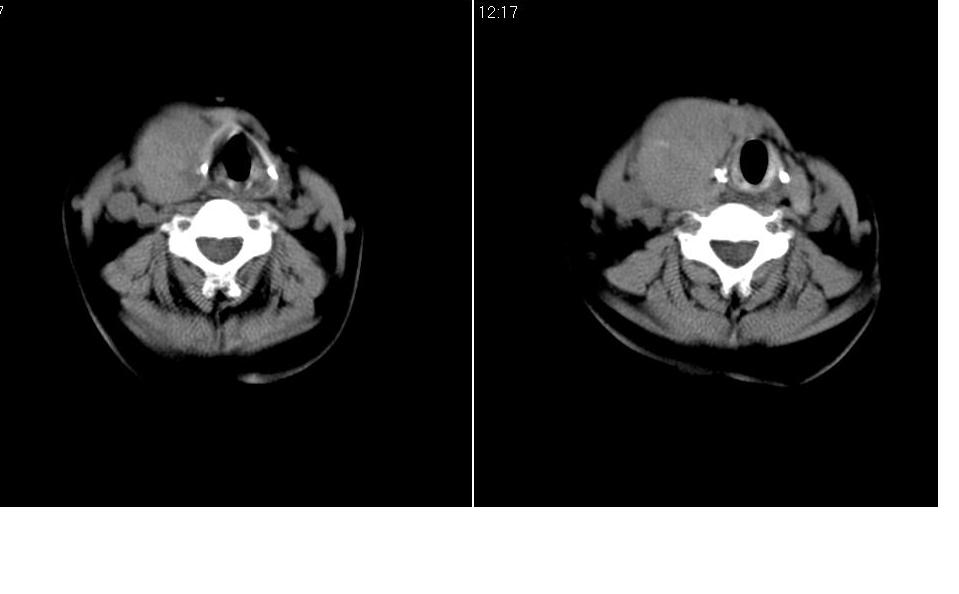

标题: CT27207:颈部CT平扫

女 55岁 右侧颈部包块十年余,自己感觉有增大。

边缘清晰光滑,偏向于甲状腺瘤。

来源于右侧甲状腺  边界清晰,内可见点状钙化,向下生长达前上纵隔血管间隙内  考虑甲状腺腺瘤并胸内甲状腺肿